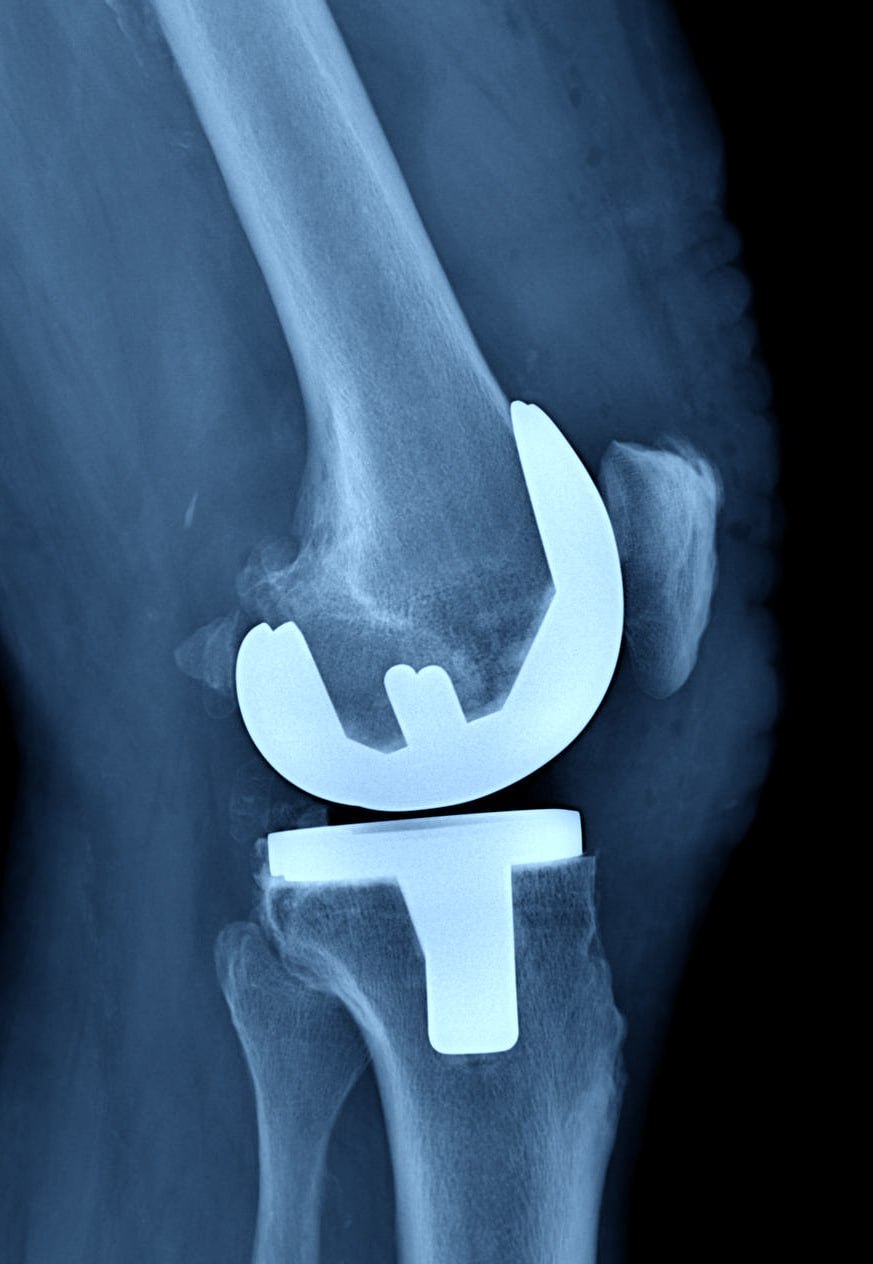

В Балахнинской ЦРБ начали выполнять операции по замене коленных суставов

На счету балахнинских врачей уже пять таких операций для людей с разрушенными коленными суставами.

Чаще всего артроз развивается из-за лишнего веса, перенесённых вирусных инфекций, сверхнагрузок, влияет и наследственность. После замены сустава исчезает боль, восстанавливается объём движений в суставе и способность опираться на ногу.

В больнице пациенты проводят не более недели, реабилитация после замены суставов занимает около 3-4 месяцев. Операции проводятся бесплатно, по полису ОМС, сообщает главный редактор ИА "Стационар-пресс" Алексей Никонов.